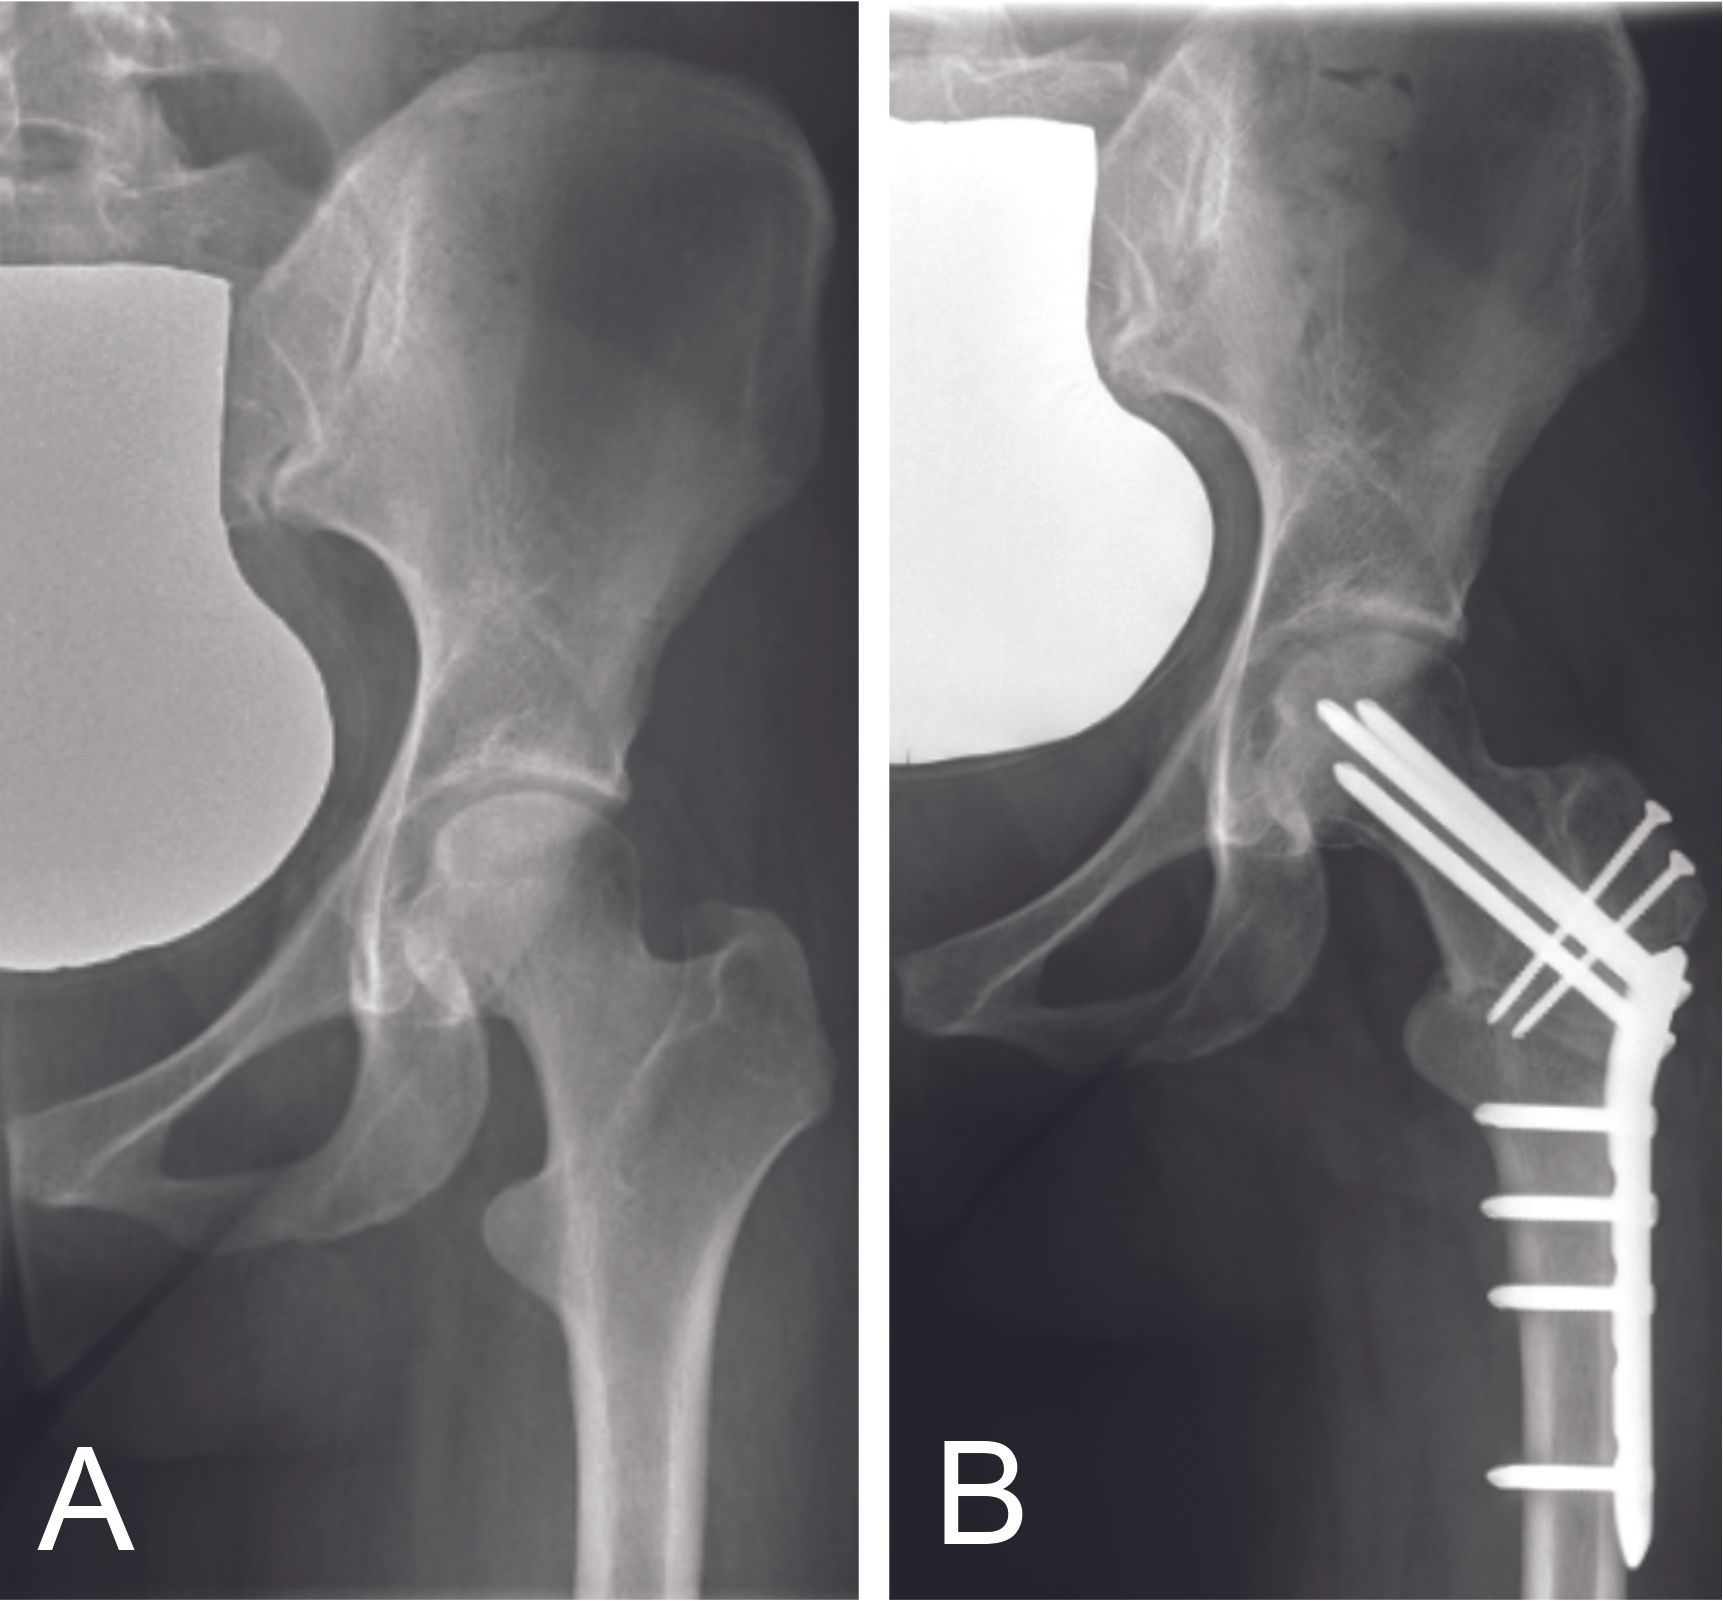

The femoral derotation osteotomy is performed through a lateral hip approach with a subvascular passage. The femoral osteotomy is performed at the subtrochanteric or intertrochanteric level (in case of an associated varus osteotomy) and stabilized with a plate (figure 13). Partial loading is recommended after surgery to protect the osteotomy.

A femoral internal derotation osteotomy may be proposed in cases of anterior FAI where there is femoral retroversion (<0°). In this case, the distal fragment will be internally derotated to increase internal rotation. A femoral external derotation osteotomy can also be proposed in cases of posterior FAI where, conversely, exaggerated femoral anteversion (>35) exists. The purpose of this external derotation osteotomy of the distal fragment is to increase external rotation. Imaging with torsion measurement is therefore essential, as well as a dynamic 3D examination to check for anterior or posterior FAI.